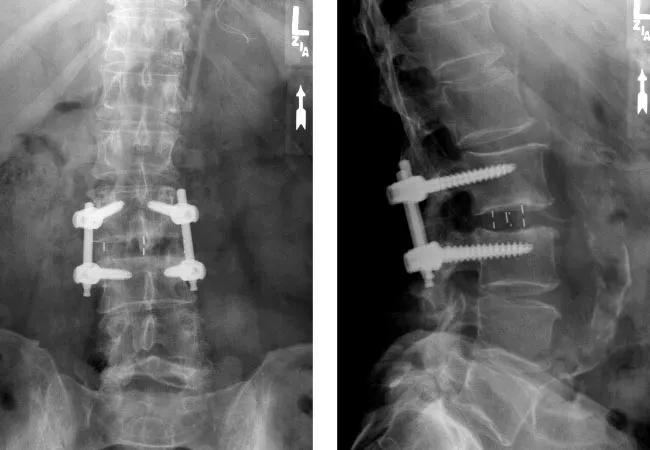

Limiting purchases of spinal implants to a single vendor can yield substantial cost savings for a large hospital system without compromising the quality of patient care, suggests a large retrospective cohort study from Cleveland Clinic.

“We chose lumbar interbody fusion as a proxy for the general quality of care at our high-volume spine center, which performs over 3,500 operations annually, because of the large number and relative homogeneity of these cases,” explains Dr. Steinmetz. Patients with a prior spinal fusion or receiving multilevel or anterior interbody fusion were excluded.